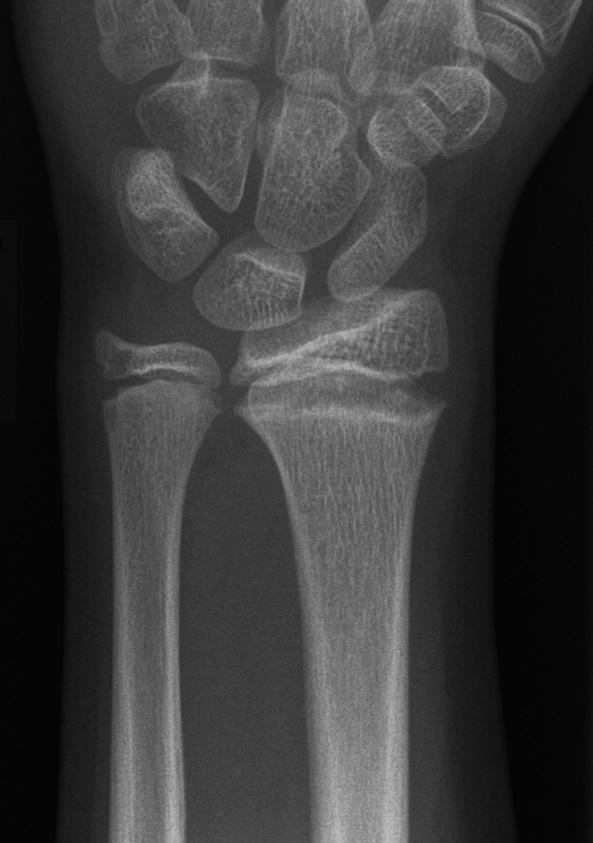

Een 11-jarige turnster kwam op de polikliniek Sportgeneeskunde, omdat zij sinds 1 jaar pijnlijke polsen had. Patiënte vertelde dat de pijn tijdens en na elke training optrad. Anamnestisch was er geen evident trauma bekend. Bij lichamelijk onderzoek zagen wij een niet-afwijkende stand van de polsen, zonder zwellingen of bewegingsbeperkingen. Alle weerstandstesten waren positief, maar de kracht was onverminderd.